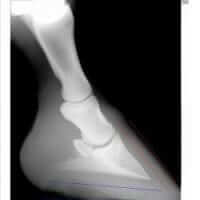

Navicular Disease In the Horse

Equine Navicular Disease has many names, including Navicular Syndrome, caudle heel pain as well as podotrochleosis.  The condition is all too common to many horse owners, unfortunately, and can significantly impact performance, general movement and overall quality of life due to pain generally located in the heel region of the front feet.  Navicular Syndrome can be difficult to manage, especially in the advanced stage, but through a combination of approaches, including nutrion and herbs, the outcome for the patient can be improved.